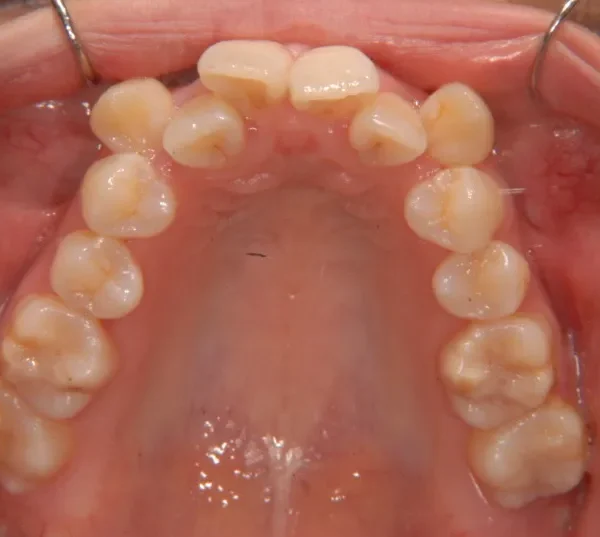

【大人の矯正】叢生・八重歯・ガタガタ・癒合歯・ピエゾサージェリー・26歳女性【M.H様】

初診時年齢 19~29歳 (女性) 主訴 八重歯・ガタガタ・癒合歯

診断名 叢生 装置名

八重歯で笑うと尖った歯が目立ちます。

上下ガタガタで、下の歯は癒合歯(2本がくっついて1本の歯)です。

初診